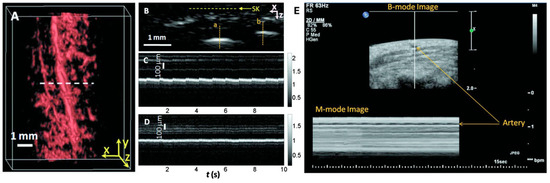

The team conducted scans on a palm region near the wrist where a prominent artery at 1 mm deep was used to investigate pulsatile dynamics as shown in Figure 6A. The 3D image was first captured and then the scanning probe was affixed to conduct a real-time B-scan lasting 10 s (see Figure 6B). Due to the strong light absorption of hemoglobin at 570 nm, the lower portion of the artery was less visible. Nevertheless, the team successfully recorded the motion dynamics of arterial pulsation. An M-mode image through the artery’s center is displayed in Figure 6C. The estimated pulsatile rate from this image was 66 beats per minute, consistent with the 65 ± 2 beats per minute measured by a pulse oximeter. For comparison, an M-mode image of a vein was shown in Figure 6D, which disclosed relatively weak motion in the vein, presumably induced by skin movement caused by arterial pulsation. The team also noted that in the ultrasound image (Figure 6E), the M-mode image revealed that the artery predominantly expanded in a direction perpendicular to the skin surface, with only minimal expansion observed parallel to the skin surface. Although both PA and US M modes can detect pulsatile activity, the waveform origins differ. Pulsatile signals from PA M mode included both arterial position vibration and optical absorption, while those of US M mode were only induced by tissue movement from the same region.

Figure 6. Dynamic in vivo photoacoustic and ultrasound imaging using a PACT system (reproduced with permission from Ref. [33]). (A) Volumetric photoacoustic image of a human hand, with dashed line indicating the cross-section for real-time B-scan imaging. (B) B-scan image corresponding to the horizontal dashed line in (A), showing skin surface (SK). (C) M-mode image along vertical line a in (B), demonstrating time-resolved arterial pulsation. (D) M-mode image along vertical line b in (B), showing venous dynamics. (E) Corresponding ultrasound images of arterial pulsation.